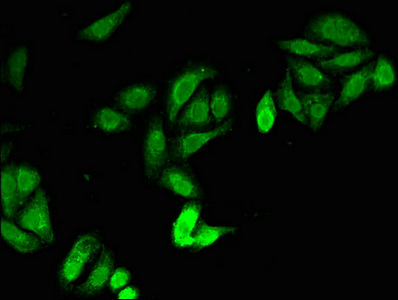

Immunofluorescent analysis of HepG2 cells using CSB-PA01949A0Rb at dilution of 1:100 and Alexa Fluor 488-congugated AffiniPure Goat Anti-Rabbit IgG(H+L)